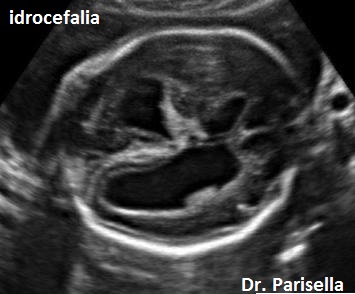

1. ventricolomegalia,